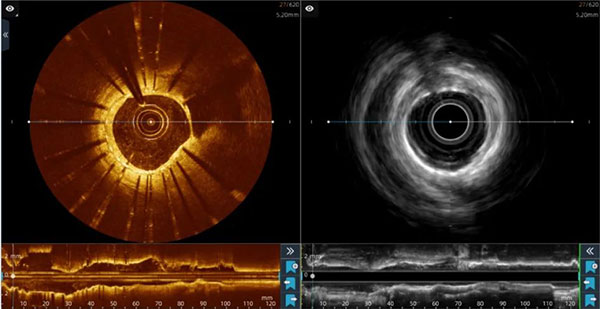

大家看到这张图片会想到什么?是不是很像机器人的两只眼睛?如果告诉您这是我们心脏血管内的影像图片,您会不会问这是同一个人的吗?怎么还不一样啊?这个血管怎么啦?等等问题。

正如我们前面看到的图片,“IVUS-OCT二合一冠状动脉腔内成像技术”是我国自主研发的国际上第一款双模IVUS-OCT一体机。它实现了一次检查,同时获得血管内超声(IVUS)和光学相关断层成像扫描(OCT)两种检查的影像结果,为心血管临床诊断和治疗提供了更科学、高效、精准的影像学依据。

目前,血管腔内的影像学检查主要包括血管内超声(IVUS)检查和光学相关断层成像扫描(OCT)检查。这两种检查各有利弊,血管内超声(IVUS)检查穿透力强且成像更深,能够看到血管壁的中膜和外膜,从而掌握血管腔内的真实信息,特别适合血管存在斑块、出血和钙化的情况。但是,其影像分辨率差,无法清楚显示支架内膜是否覆盖、是否存在血小板聚集等情况。光学相关断层成像扫描(OCT)检查的优点在于高分辨率,可以对支架贴壁、内皮覆盖及血小板聚集等情况清楚的显示出来,方便帮助医生更好的判断病情,但是不能穿透血管壁看到更深处的病变。

在检查中发现,王阿姨病变血管存在显著钙化,血管中的支架存在贴壁不良的情况,并且管壁存在正性重构,血管支架的小梁确实存在内膜覆盖不全,没有发现血小板聚集等血栓形成情况。结合患者病情及IVUS/OCT双模检查结果,张健主任团队对王阿姨进行了针对性处理,并调整了治疗方案。手术后,王阿姨的症状得到了明显缓解。